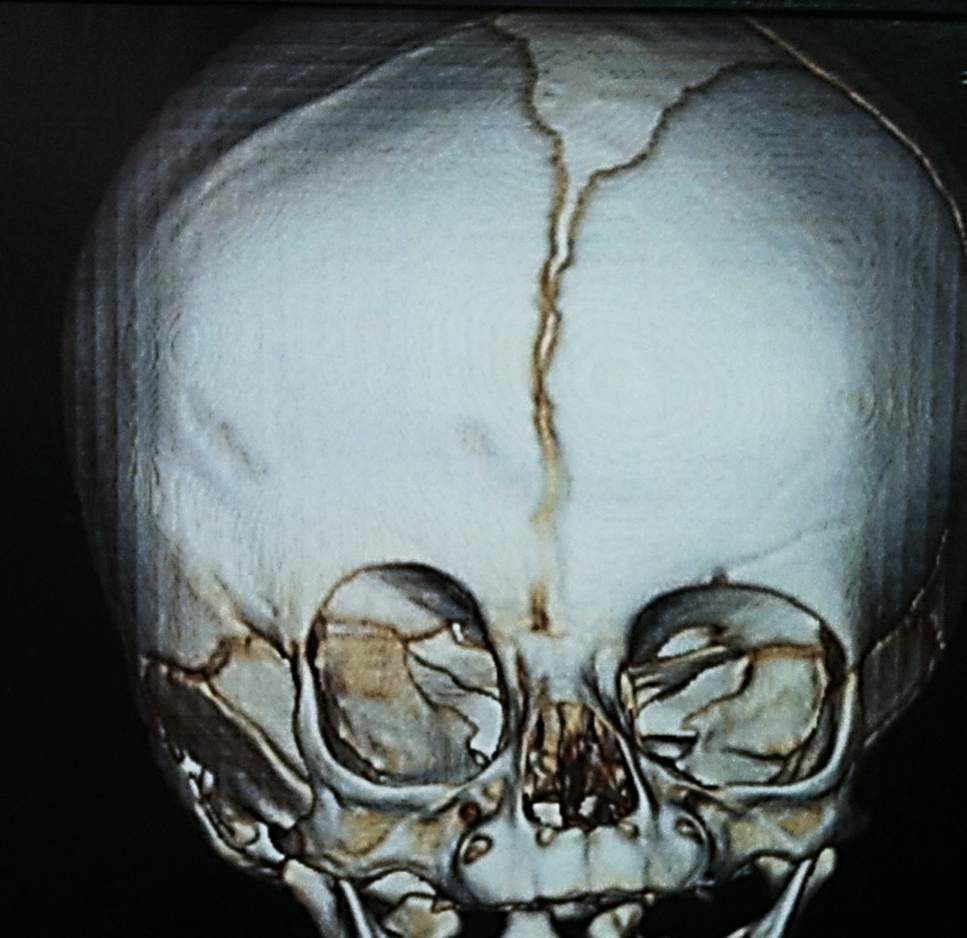

> Escafocefalia, é a sinostoses mais comum, vista mais no sexo masculino,o que acontece é o fechamento da sutura sagital levando o crânio ao formato de barco. A cirurgia é indicada de preferencia antes do sexto mês de vida, mas se a criança tiver mais idade, não impede de ser operado.